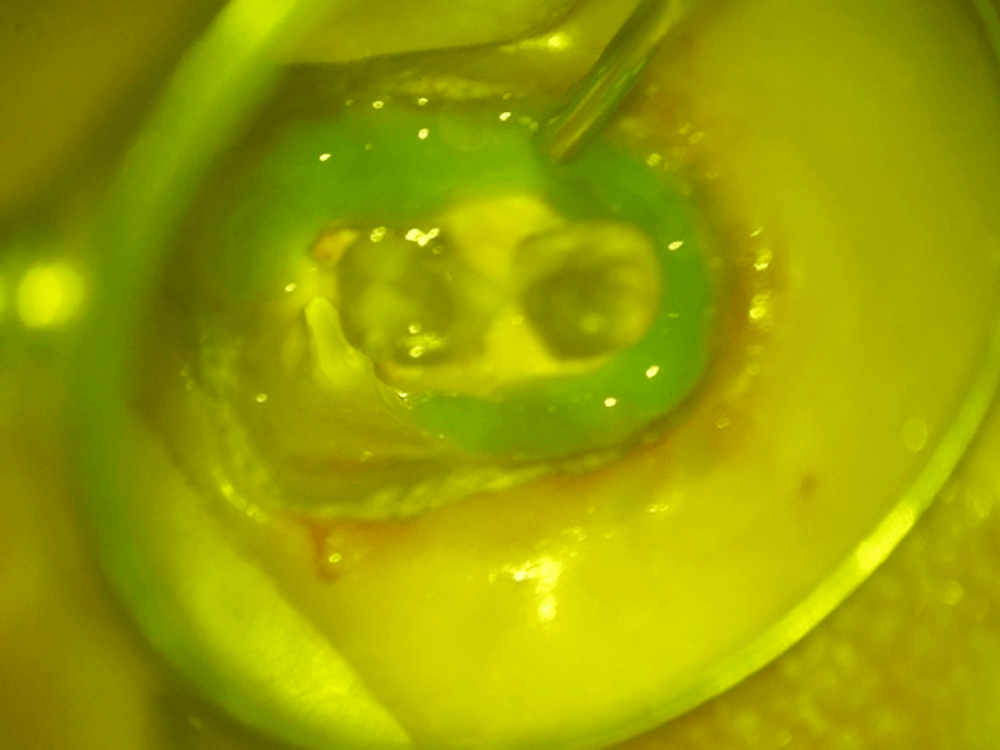

虫歯が残っている部分を染め出します。また、ヒビが入っているのがわかりました。

ラバーダム

もしも歯髄が出てしまった場合に、その歯髄が唾液に暴露し、感染してしまうと、歯髄が残せなくなってしまうため、そのリスクを軽減する意味で、ラバーダムが必要になります。